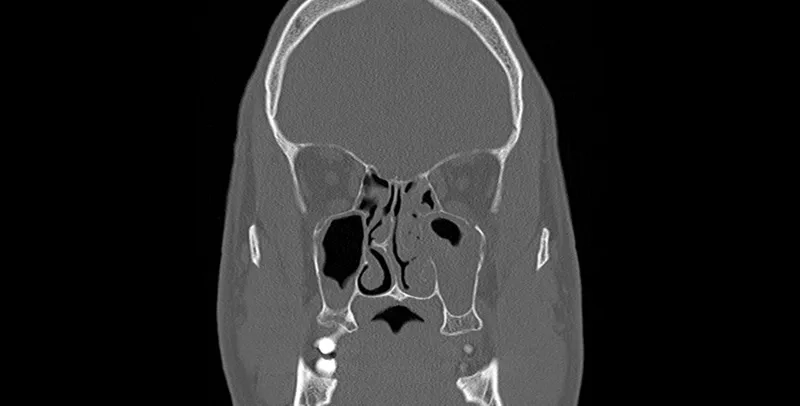

• Nasal polyps, which are soft, noncancerous growths on the lining of the sinuses, can block nasal passages and lead to chronic inflammation.

• A deviated nasal septum, the wall between your nostrils, can obstruct one or both sides of your nose, preventing proper sinus drainage.

Image of the disease chronic sinusitis and other variables